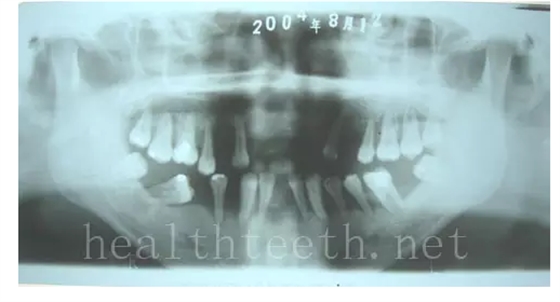

3、多生牙

病例1

QQ圖片20150722094304.png

QQ圖片20150722094321.png